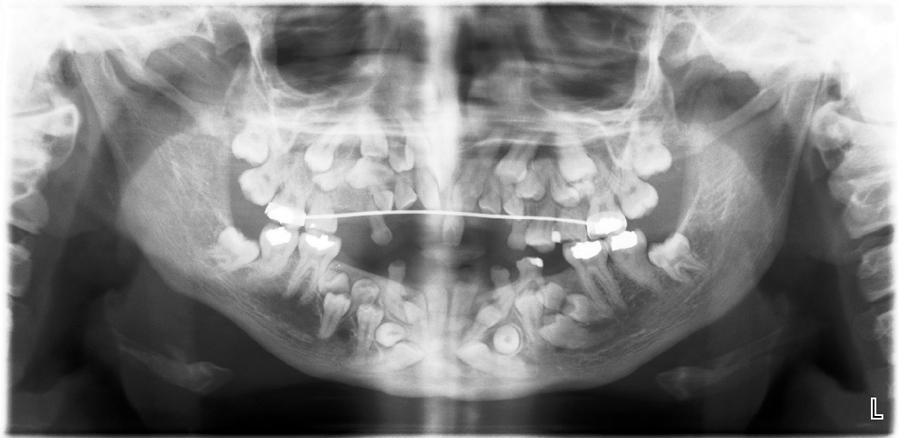

This pano looks good right? No. What does this patient have?

cleidocranial dysplasia